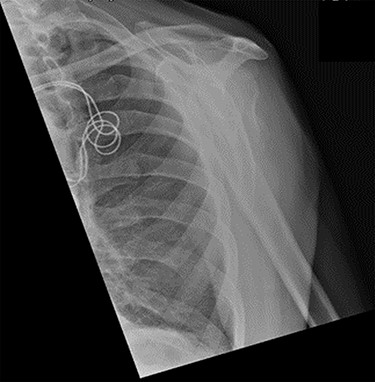

An X-ray of the left shoulder was performed, which revealed acceptable positioning of the fracture. Following a discussion with the patient, a mutual decision was made to manage the injury non-operatively and he was discharged with a collar and cuff sling. Subsequent clinical and radiological review at 1 week and 2 weeks post-injury showed the soft tissues to be healing well and the fracture to be well-positioned (Figs 5 and 6).

Antero-posterior view X-ray taken 2 weeks post-injury showing acceptable positioning of the fracture.